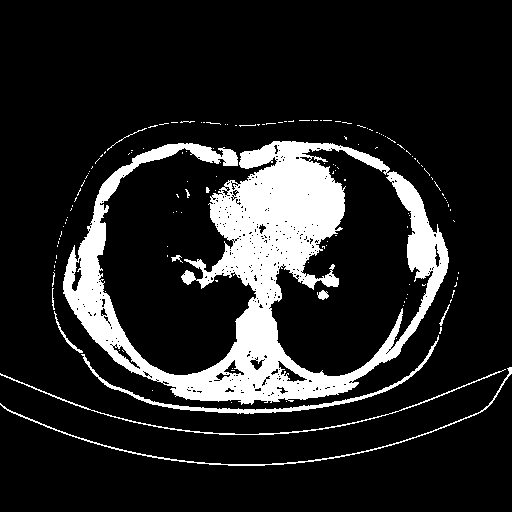

Reconstructed NATIVE CT scan (cycle consistency)

Full window (WL 1023.5, WW 4095 β†’ Low βˆ’1024, High +3071)

Actual HU range: [-1024.0, 3071.0]